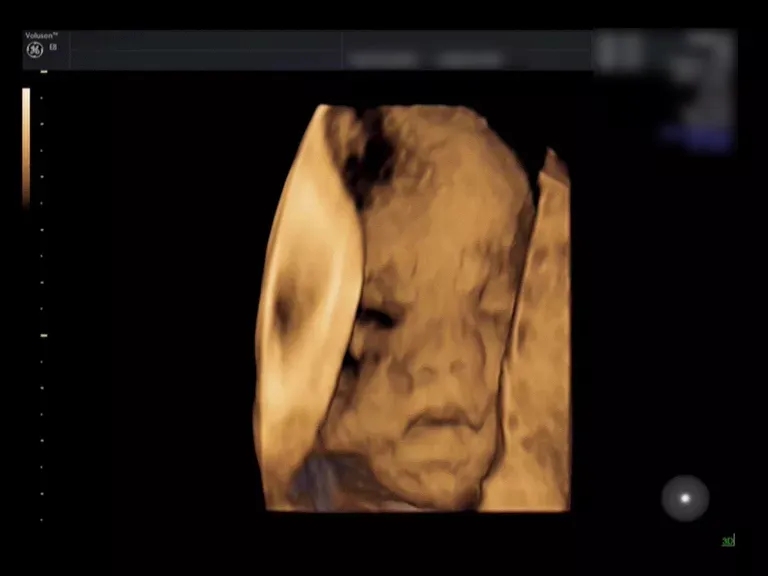

三维彩超能直观立体地显示人体器官结构

而二维成像技术只能显示人体器官的某一切面

来看这个小baby的彩超对比

就一目了然啦

(三维超声)